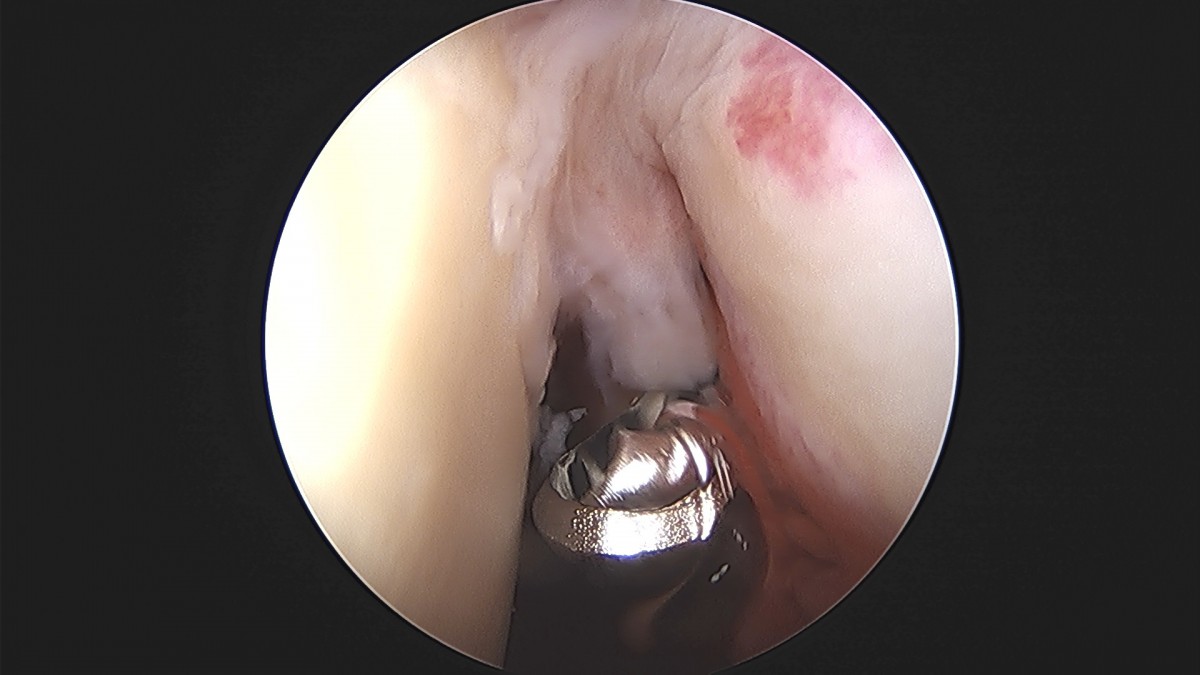

이재상원장님 어깨 견봉하 감압술 및 관절낭 이완술 박창O 환자

dae765e4d9ac96aee867c9d6292d8784_1758004612_2234.jpg